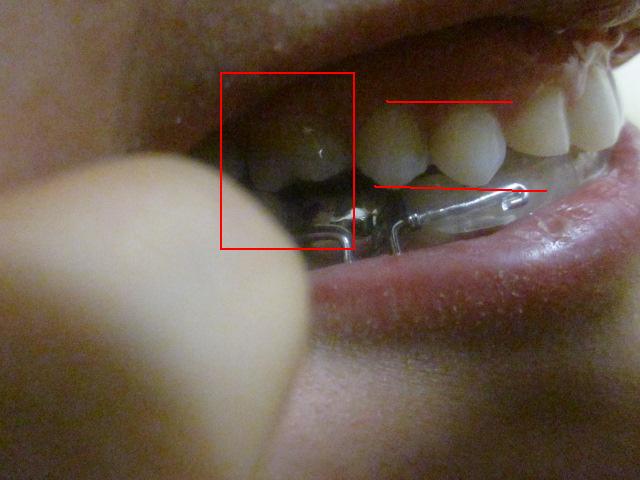

치료 막바지 입니다. 그런데 이게 교정이 잘되고 있는게 맞는건지 이제 장치 빼자 하면서 6개월이 흘렀고 이번 토요일에 빼자 하고 있습니다 아직 마음에 안드는게 많은데 엑스레이도 안찍어 보고 그냥 배열만 보고 ...